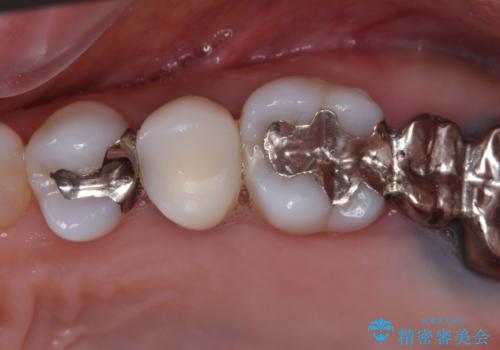

- 奥歯の銀歯とクラウンの縁から見えている歯根を気にして来院された患者様です。

歯根の見えている歯はセラミッククラウンに、詰め物の銀歯が入っている歯はセラミックインレーにて治療を行うこととしました。